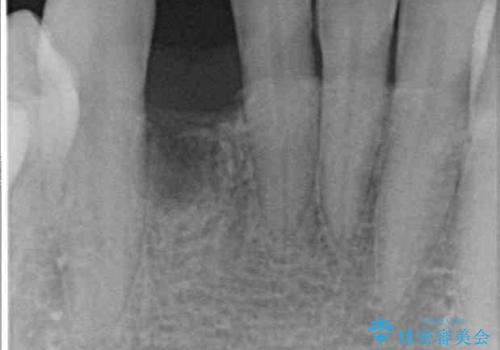

インプラント治療に際し、前歯の叢生に対する矯正治療を提案したところ、興味を持たれたので、インビザライン・ライトによる矯正治療を行うこととしました。

抜歯後にスペースができると恥ずかしいため、抜歯した歯を接着剤で固定した上で矯正治療を行い、その後インプラントやオールセラミッククラウンの装着を行うこととしました。